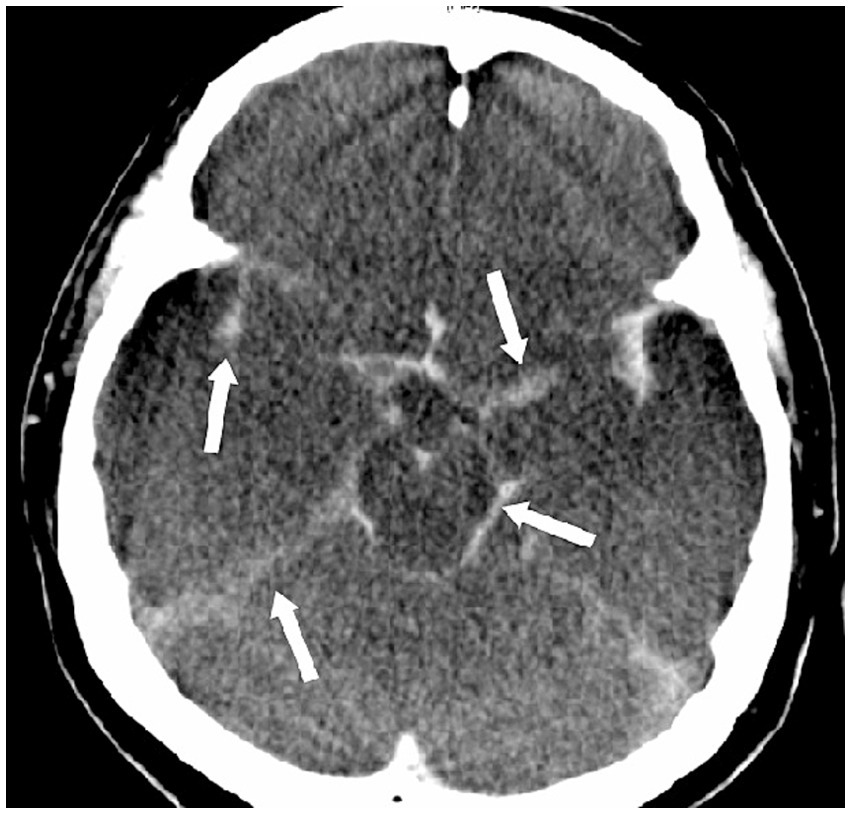

Figure 5

Pseudosubarachnoid hemorrhage. This 47-year-old man suffered from sudden cardiac arrest in a supermarket. Cardiopulmonary resuscitation was initiated by his friends until the arrival of paramedical professionals. Initially noted ventricular fibrillation was successfully cardioverted by two electric shocks, and he was intubated and brought to our emergency room (downtime 36 min). No brainstem reflexes were observed. The CT scan of the brain showed increased attenuation within the basal cisterns that mimics a subarachnoid hemorrhage.